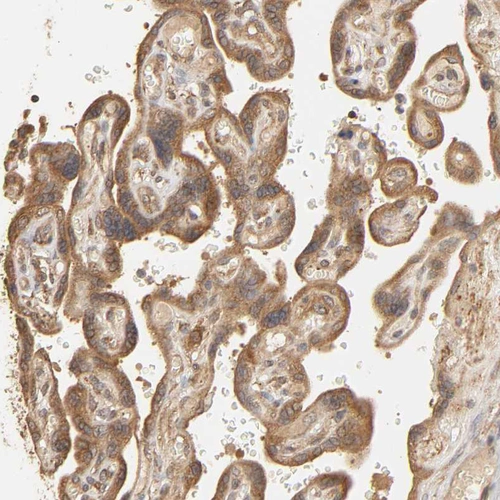

Immunohistochemical staining of human kidney shows moderate cytoplasmic positivity in cells in tubules.